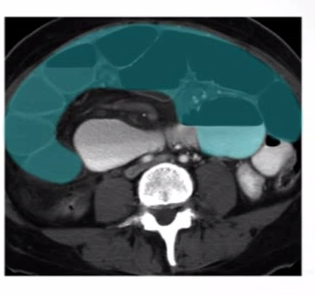

What is this showing…?

SBO 2/2 hernia

-see dilated bowel (blue and yellow) up to rapid transition point, w/ collapsed bowel (red) right after herniated portion of bowel